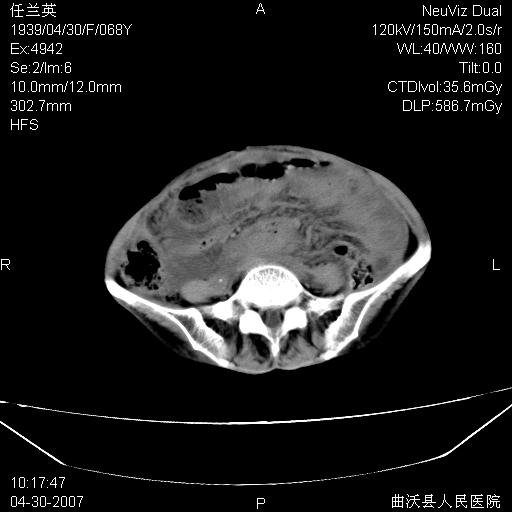

患者,女,68岁,感觉腹部憋涨发硬数天,查b超发现左盆腔有囊性肿物和少量腹水,行ct检查

1.考虑卵巢肿瘤并腹腔广泛性转移可能性大;

2.腹盆腔少量积液。

支持左侧卵巢恶性肿瘤伴网膜、腹膜广泛转移。

难的一见 典型 - 网膜饼  冰冻骨盆 可以当教学片了